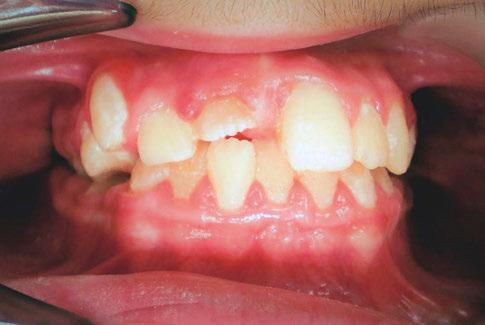

An 8-year-old Hispanic male presented to our private practice in Miami, Florida with the chief complaint of a missing front tooth (Figure 1). Upon review of his medical history, the mother revealed that her son had Autism Spectrum Disorder and confirmed that his condition was severe. This patient did not take

Figure 1: Face of 8-year-old patient at initial consultation

PEDIATRIC BENCH BOOSTER SEAT P3000LS TREATMENT CHAIR

any medications, was nonverbal, avoided eye contact with any staff member including the treating pediatric dentist, did not sit in the dental chair, and was constantly tapping his ears. No dental radiographs were obtained due to his uncooperative behavior. For the dental exam, the mother agreed and consented with placing him in a passive restraining device. With a limited visualization of his oral cavity, a mixed dentition was noted. The maxillary right permanent central incisor was absent. No significant pathology was found in his oral soft tissues. Dental caries was found on both primary and permanent molars. A decision was made to complete dental treatment using general anesthesia as a behavior management technique at the local children’s hospital.

The following procedures were accomplished under general anesthesia on an outpatient basis — full mouth dental radiographs and a comprehensive oral exam. A complex odontoma was found to be the etiology of the noneruption of the maxillary right permanent central incisor (Figure 2). Since dental caries also was diagnosed, a full-mouth prophylaxis was completed. Dental caries was controlled, and teeth were restored. A 5 mm incision was made on the gingiva over the impacted maxillary right permanent central incisor, and two tooth-like structures were extracted from the right maxillary incisor area. A postoperative periapical radiograph was taken to confirm complete odontoma removal (Figure 3). Three interrupted sutures using 3-O chromic gut were placed.

At the postoperative consultation with the mother, we told her the tooth’s complete root formation might prevent its eruption. Orthodontic extrusion of the incisor was ruled out due to his behavior. A conservative approach with observation only was elected as treatment modality. This patient returned for follow-up appointments at ages 10, 11, 12, and 13. During all these visits, the maxillary right permanent central incisor had not erupted. At age 14, due to recurrent dental caries, the patient was taken to the local children’s hospital for dental rehabilitation again. During this second hospitalization, we noticed that the right maxillary central incisor was partially erupted into the oral cavity (Figure 4).